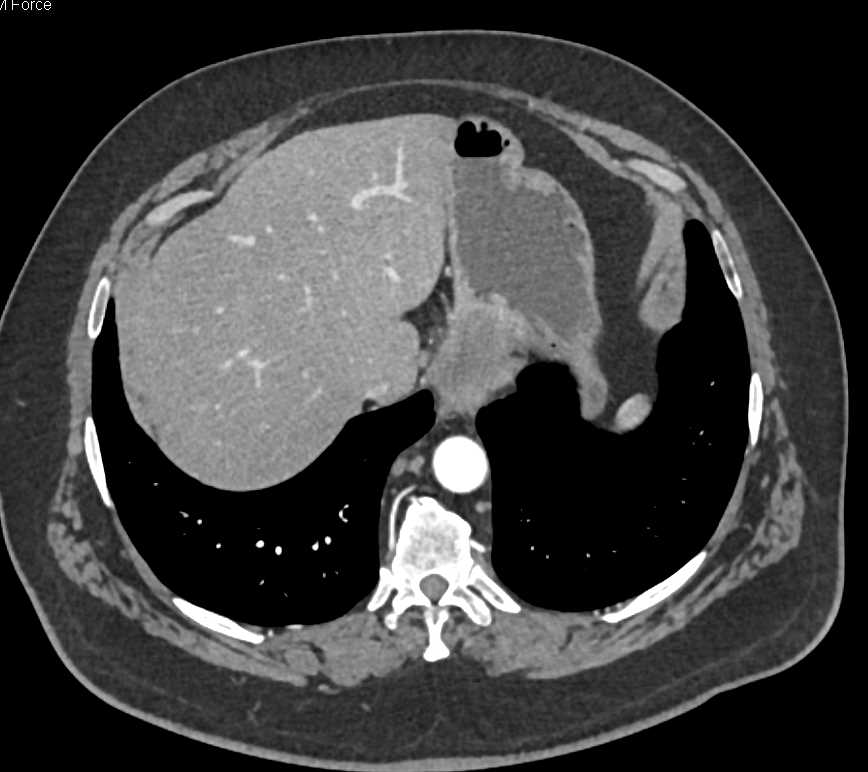

Gastric GIST Tumor